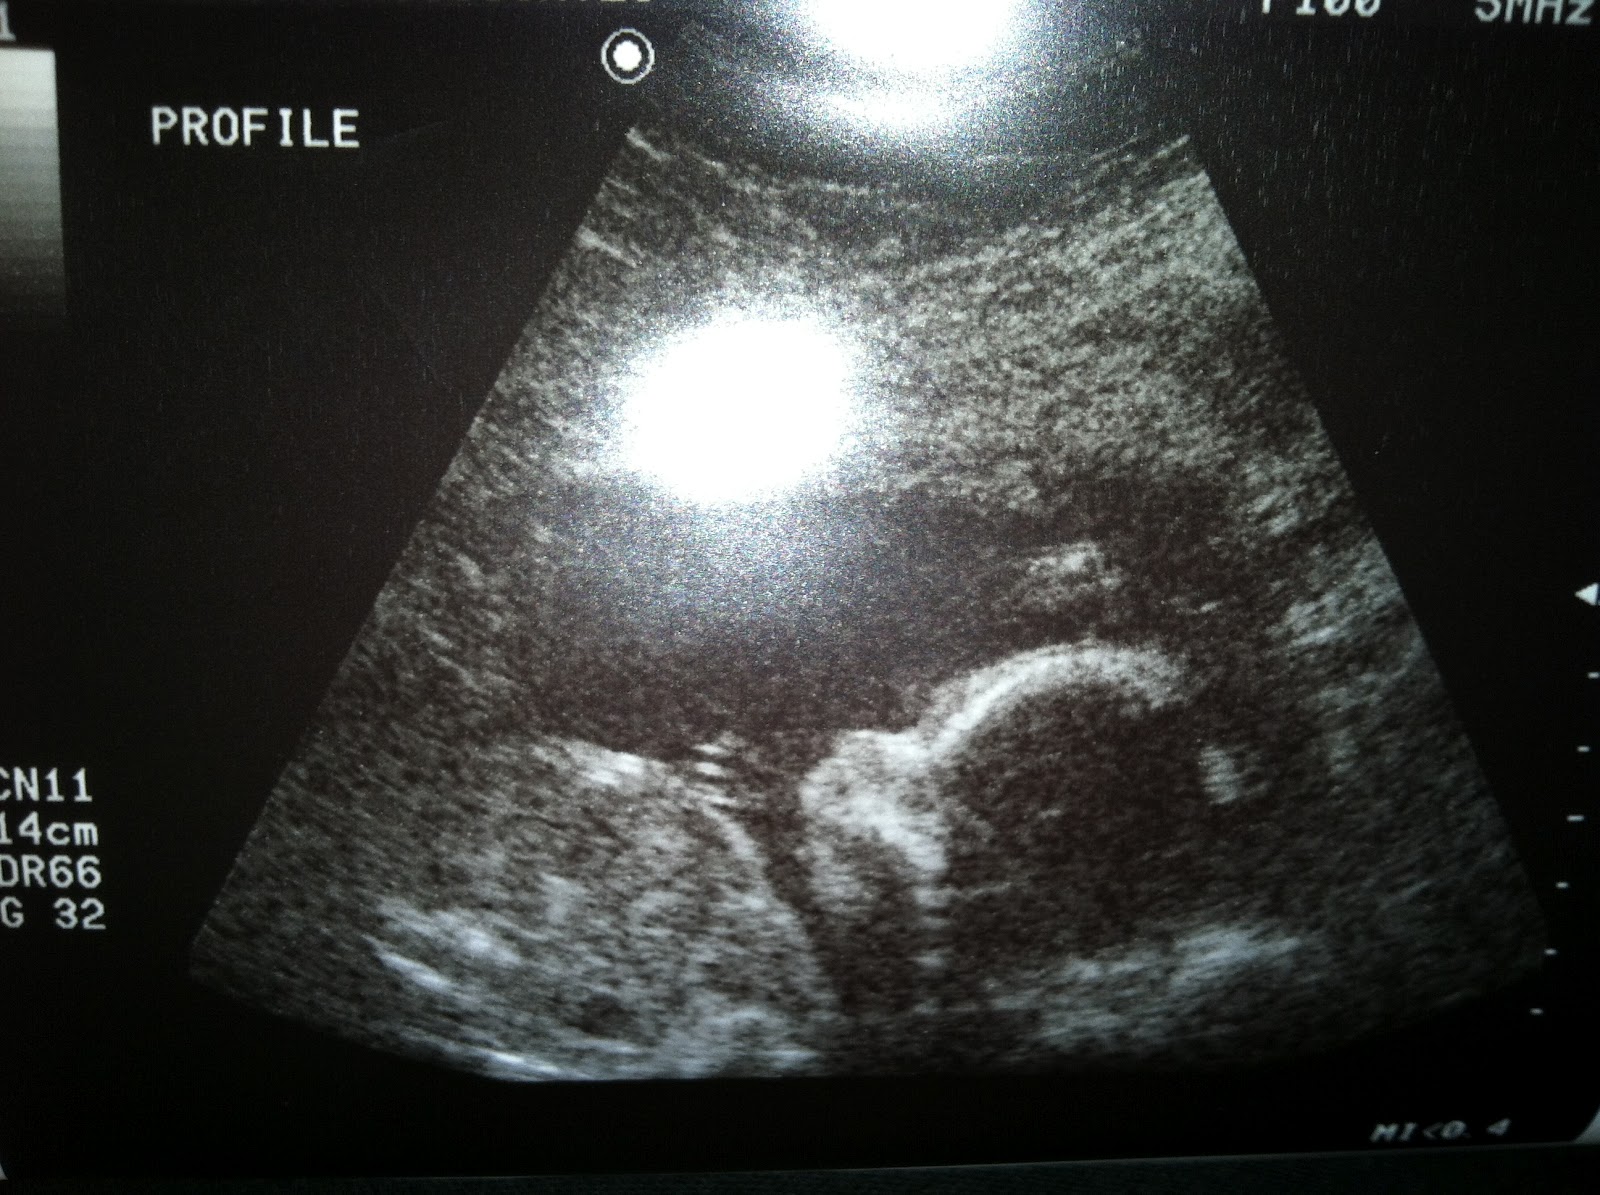

Baby William "Liam," 20w 3d

So far I'm feeling pretty good. I didn't really have that bad of morning sickness, except for some migraines that had my tossing my cookies, and while I was at work. Apparently 1am was not a good time to be awake. Baby Liam is active and kicking. At our 20w ultrasound he was measuring right on track, except for his limbs. Both arms and legs were measuring a full week and a half a head of the rest of him. So we're thinking he's going to be one tall kid.